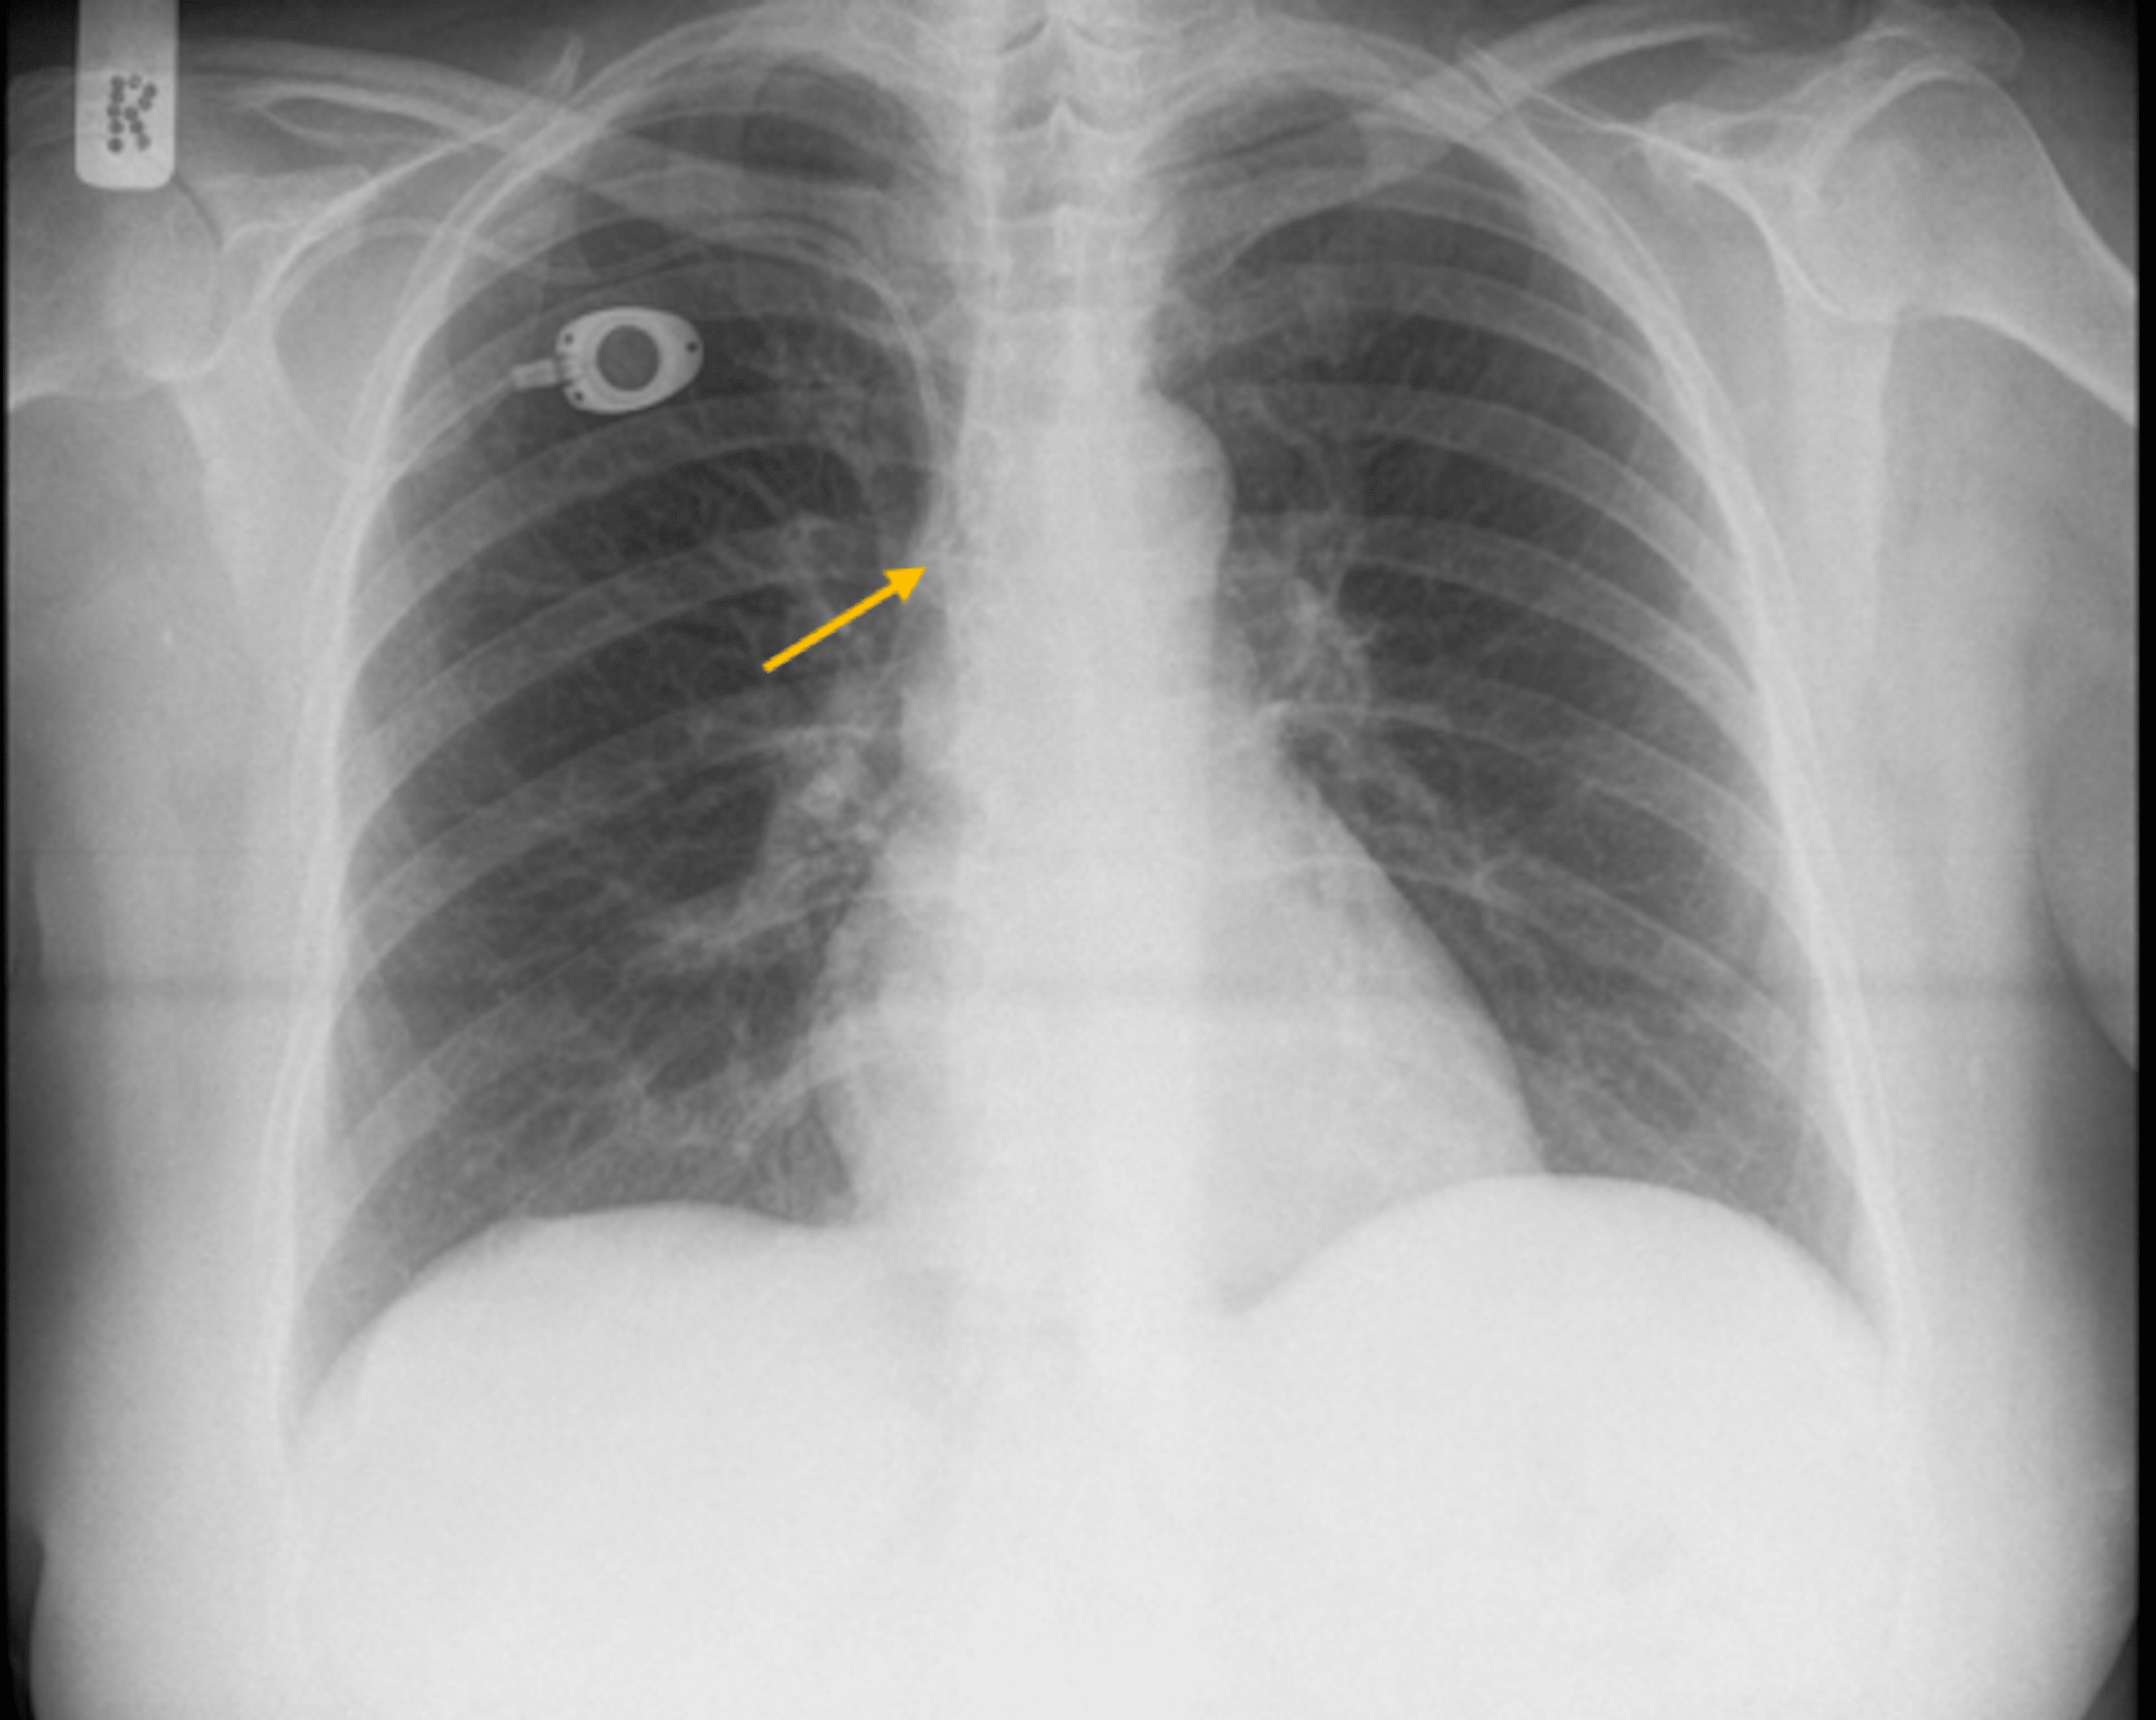

Chest Xray showing catheter fragment in the internal jugular vein. The Internal Jugular Vein Catheter Radiology Summarize the complications of internal jugular vein cannulation. 4 it has a straight course to the right heart, the lowest risk of symptomatic central venous stenosis and thrombosis. the internal jugular vein (ijv) is the major venous return from the brain, upper face and neck. if fluoroscopy is not used during catheter insertion, a malpositioned catheter may lie. Internal Jugular Vein Catheter Radiology.

Radiograph shows a catheter kink (arrow) at internal jugular vein exit Internal Jugular Vein Catheter Radiology 4 it has a straight course to the right heart, the lowest risk of symptomatic central venous stenosis and thrombosis. the preferred vein for cvcs is the right internal jugular vein. the internal jugular vein (ijv) is the major venous return from the brain, upper face and neck. cvcs are most commonly inserted via the right internal. Internal Jugular Vein Catheter Radiology.

Radiograph of a right internal jugular tunneled central venous catheter Internal Jugular Vein Catheter Radiology Summarize the complications of internal jugular vein cannulation. Right internal jugular catheters are positioned on the right. explain how to insert an internal jugular catheter. 6), contralateral subclavian or axillary vein, or azygous. the internal jugular vein is a continuation of the sigmoid sinus as it emerges from the jugular foramen at the skull base. It is formed. Internal Jugular Vein Catheter Radiology.